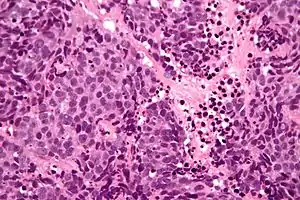

| Micrograph of a sinonasal undifferentiated carcinoma. H&E stain. | |

Low mag.

High mag.